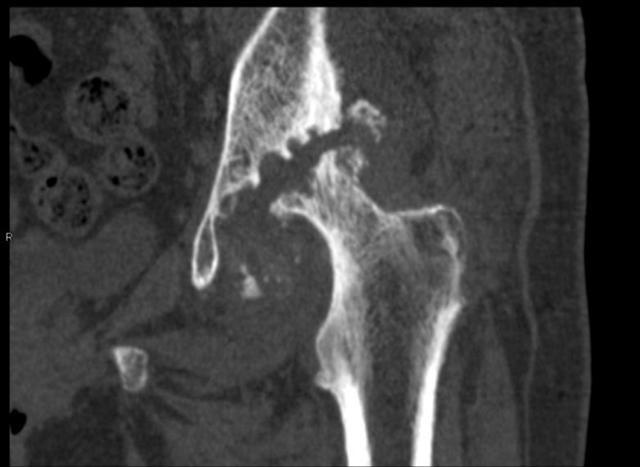

骨頭的空隙處是已經(jīng)消失缺損的髖臼。

70歲的彭阿姨家住漢陽(yáng),一周前她因髖部疼痛劇烈,無(wú)法行走,被子女送到武漢市第一醫(yī)院骨科住院治療。管床醫(yī)生張麟檢查發(fā)現(xiàn),彭阿姨的左腿比右腿短了3厘米,片子上左側(cè)股骨頭已經(jīng)消失看不見(jiàn)了。

剛開(kāi)始,她感覺(jué)腿舒服了不少,一段時(shí)間后疼痛反復(fù)且更加嚴(yán)重,以為是藥量不夠,就加量服用。沒(méi)想到現(xiàn)在痛得連路都走不了。彭阿姨最終確診為左側(cè)股骨頭無(wú)菌性壞死,髖臼缺損,接受左側(cè)髖關(guān)節(jié)置換術(shù)后,15日康復(fù)出院。